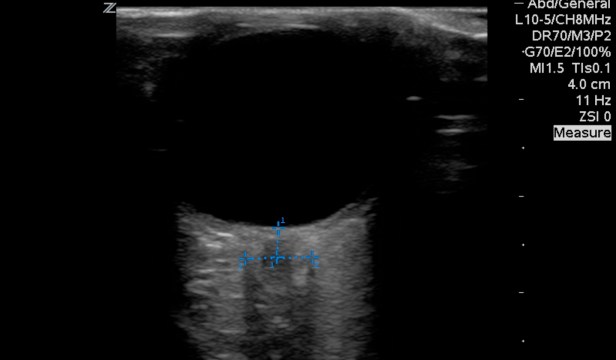

So close, but a few too many measurements. When evaluating for optic nerve sheath diameter or ONSD measure 3mm from the retina into the optic nerve. Then measure the diameter left to right. A value of more than 5mm in adults suggests an elevated intracranial pressure.